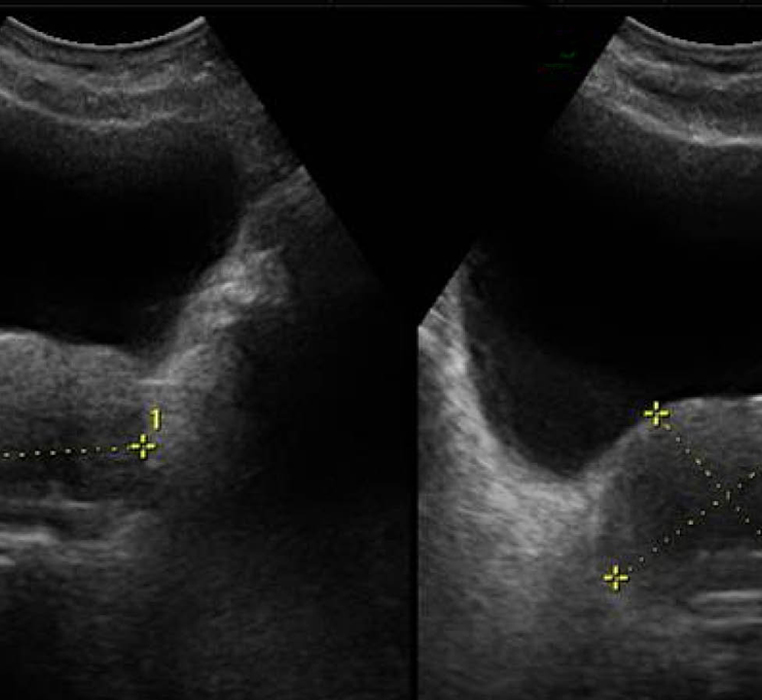

Ecografía Prostática Transrectal